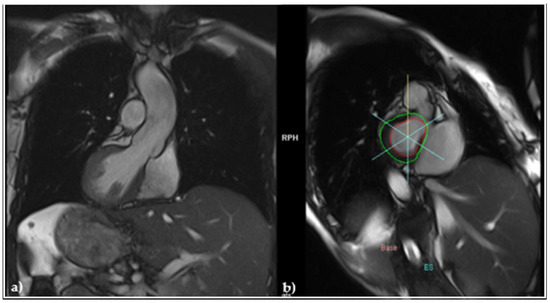

2.4. Diagnosis of Heart Failure, Initiation of Guideline-Guided Therapy, and Evolution